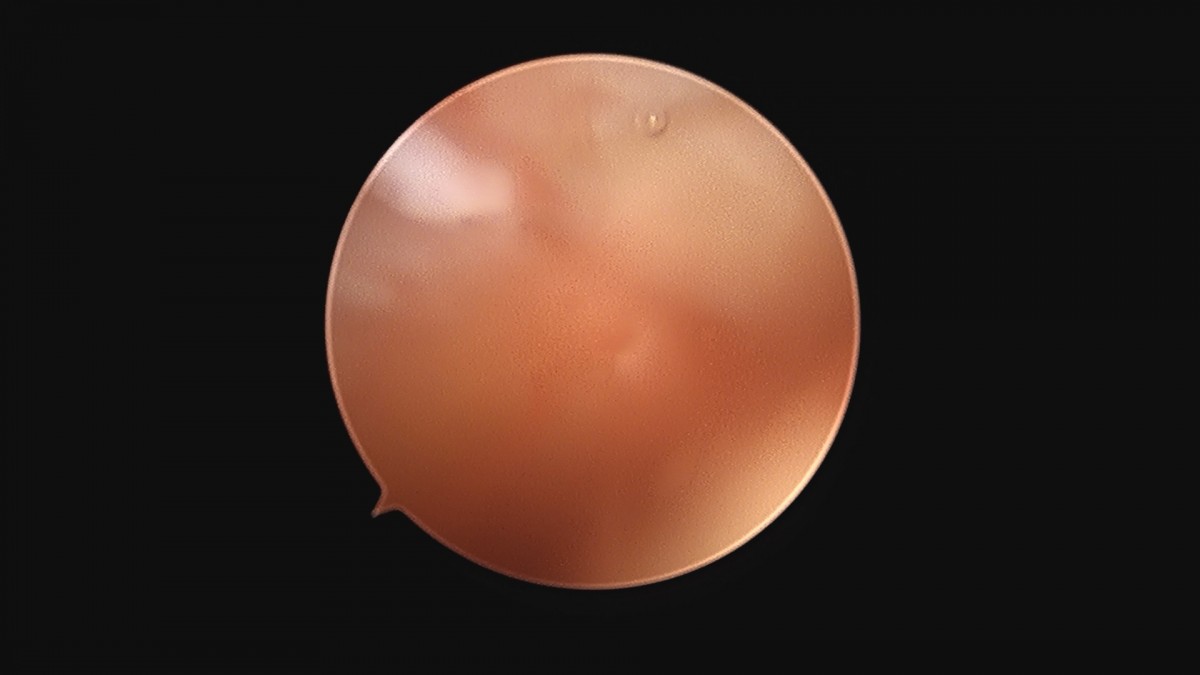

이재상원장님 무릎 변연절제술 권오O 환자

작성자 최고관리자 댓글 0건 조회 373회 작성일 25-09-16 16:11